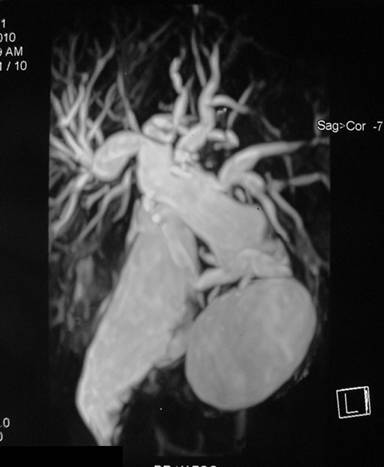

Plain X-ray of the abdomen revealed classical curvilinear calcification in only one patient with a hydatid cyst in the pancreatic body (Figure 1). Ultrasonographic examination which recorded the site, size and extent of the lesions, documented the cystic lesions as anechoic rounded structures in all cases. An abdominal CT scan documented the cysts as spherical hypodense space-occupying lesions. All the lesions were solitary, measuring 26-50 mm in diameter (mean 36.7 mm). Five lesions were cystic with thin walls and one lesion appeared as a multiseptated cyst. Magnetic resonance imaging for defining the lesion and its relationship with the pancreatic duct was performed in three patients (two lesions in the head and one in the body of the pancreas). Two lesions were located in the head (Figure 2, 3, 4, 5), two in the body (Figures 6 and 7) and two in the tail region of the pancreas (Figure 8). In two cases, a preoperative diagnosis was possible due to the presence of classical features which also included a concomitant hydatid cyst in the liver in one patient. All patients underwent surgical exploration; intraoperative cyst puncture for aspiration cytology was successful in three cases (two cases with cysts in the head and one case with a cyst in the body of the pancreas); the results of cytological examination were positive in all cases. A fragmented laminated membrane was observed in two patients, scoliosis in three and hooklets in one patient (Figure 9). The laminated membrane was seen as a foliated, acellular, pale, eosinophilic structure which stained strongly positive with periodic acid Schiff staining and negative with alcyan blue staining. The hooklets had a characteristic shape presenting as a blade, a guard and a root. They were not stained with Papanicolaou stains and their appearance was enhanced by turning down the microscope condenser. There were no complications after diagnostic aspiration. In all three cases, the aspirated fluid was colorless and contained a mean sodium level of 128 mEq/L (range: 128-130 mEq/L), chloride level of 69 mEq/L (range: 65-70 mEq/L) and potassium level of 5.8 mEq/L (range: 5.4-6.3 mEq/L). Cysts in the distal pancreas observed in the two patients were treated by a distal pancreatectomy with splenectomy. Cysts in the body were treated by a pericystectomy in one patient (Figure 10) and a central pancreatectomy in another patient. Cysts in the head region in two patients were treated with evacuation, partial cystectomy and tube drainage of the cavity after protecting the surgical area with a scolicidal solution (Figure 11). Both patients underwent T-tube drainage of the common bile duct; there was rapid regression of the jaundice in these patients. The T-tube cholangiogram confirmed the free flow of bile into the duodenum; the tubes were eventually removed in the third postoperative week. Postoperative confirmation of the hydatid cysts was obtained on the basis of the histopathological findings. There were no postoperative complications; all patients recovered uneventfully. The antihelminthic drug, albendazole, was administered postoperatively (10 mg/kg body weight/day) in all cases for a period of 6 months. All the patients were followed up at three-month intervals and each patient underwent clinical examination, abdominal ultrasonography and indirect hemagglutination tests; no patient had cyst recurrence or dissemination. The mean follow-up time was 58.7 months (range: 4-120 months).

Figure 2. Contrast-enhanced computed tomography scan showing whorled appearance of a hydatid cyst in the region of pancreatic head (thick arrow) causing atrophy of the pancreatic parenchyma with a dilated duct (arrow head) anterior to the splenic vein (curved arrow). Note another hydatid cyst in segment VI of the liver with separation of the membranes (thin arrow) (Patient #5). |

|

Figure 3. T2-weighted magnetic resonance image in the same patient showing a hypointense hydatid cyst in the pancreatic head (thick arrow) causing dilatation of the pancreatic duct (curved arrow) and separation of the membranes in the hepatic hydatid cyst (thin arrow) (Patient #5). |